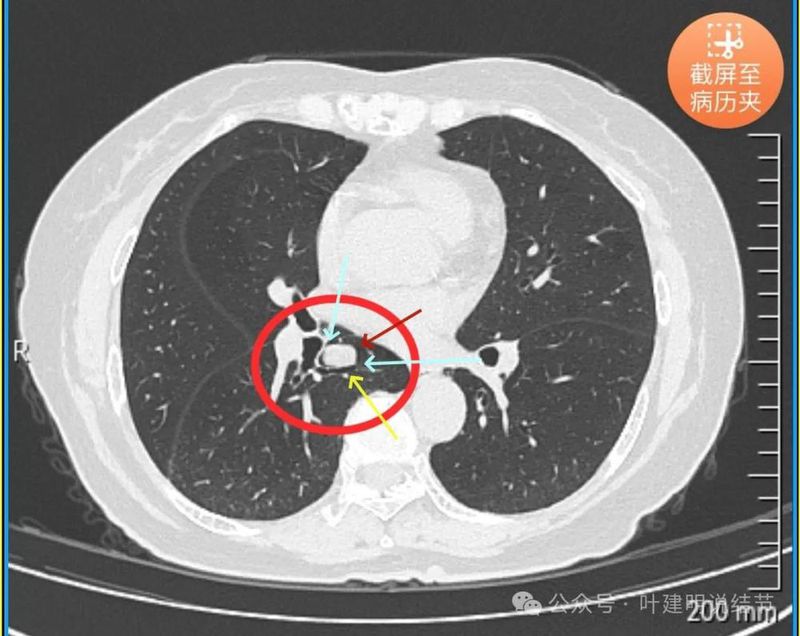

先看患者提供的2024年2月份的CT影像:

病灶出现,在右下叶支气管旁边,轮廓清楚,此层似磨玻璃密度。

表面似分叶状,密度不纯,邻近血管略有弯曲向病灶。

实性密度,边缘光滑,与背段支气管亚段贴着。

天蓝色箭头示病灶与支气管之间有缝隙,但贴的较近;黄色箭头示支气管管腔;红色箭头示病灶,边缘光滑。

支气管受压,但无明显破坏;与支气管之间紧贴位有的位置仍有缝隙;病灶边缘光滑。